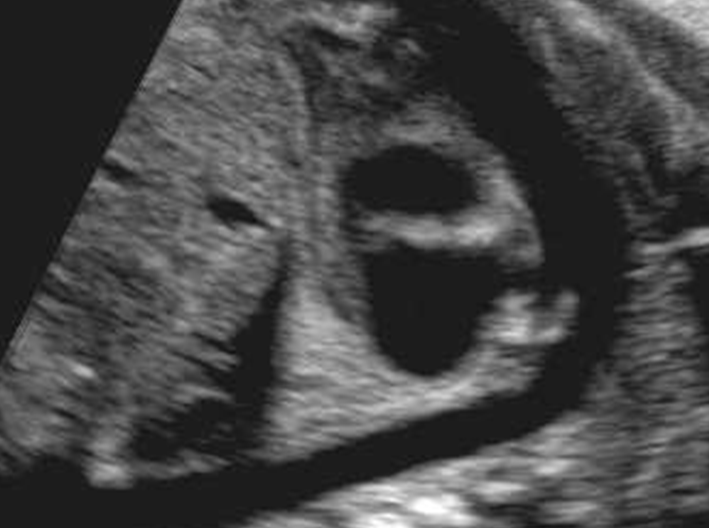

What view is this?

4 chamber view

Normal 4 chamber view